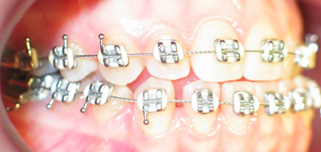

Apinhamento dentário com os dentes caninos em desoclusão (classe II, divisão 2).

Após dois anos de tratamento ortodôntico.